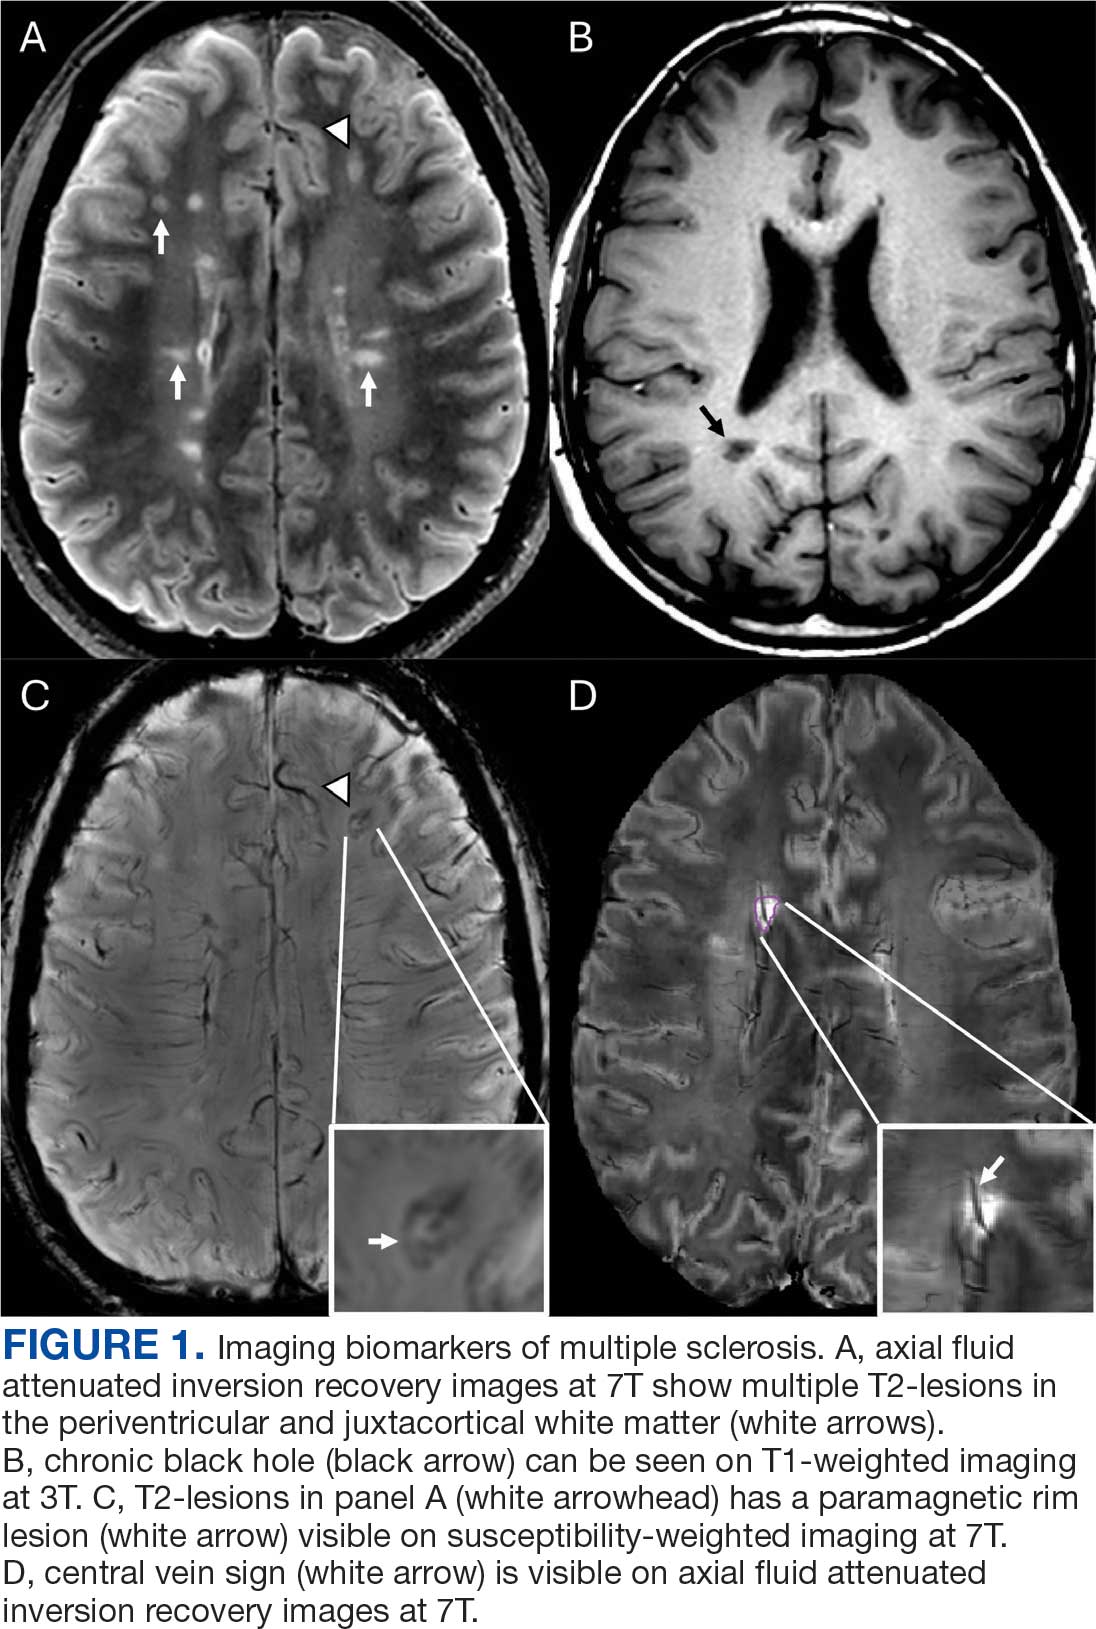

Focal immune-mediated inflammation and demyelination in MS may be detected by MRI as hyperintense foci on T2-weighted (T2-w) imaging (eg, T2-w turbo spin echo or T2-w fluid attenuated inversion recovery sequences). These T2-lesions, critical for diagnosing MS, are typically ovoid and occur in the periventricular, juxtacortical, infratentorial spinal cord white matter (Figure 1A). T2-lesion number and volume show some association with disability and optic nerve.

Select T2-lesions are also hypointense on T1-w spin echo images and are known as cBHs (Figure 1B). Histologically, T2-lesions with cBHs have more severe architectural disruption than those without cBHs.6 cBH number and volume are significantly correlated with disability, regardless of the degree of hypointensity on T1-w imaging.5,7 A 10-year longitudinal study demonstrated that cBHs were associated with disease progression after 5 years while T2-lesion volume was not, indicating that cBHs may be a more accurate predictor of disability.8

Chronic active lesions (CALs) are an important driver of PIRA. When an acute gadolinium-enhancing lesion develops in PwMS, there are 3 possible fates of this lesion. The lesion may become chronically inactive, remyelinate, or transition to CALs.14 The histopathologic signature of CALs is compartmentalized, low-grade inflammation behind an intact blood-brain barrier with evidence of both active and chronic components.15 CALs may be found not only in cerebral white matter but also in the cerebral cortex and spinal cord.16,17 Combined MRI and histopathological studies have shown that iron-laden microglia/macrophages can be detected by susceptibility-based MRI as a rim of paramagnetic signal surrounding select T2-lesions.19 These PRLs represent an in vivo imaging biomarker of CAL (Figure 1C). According to the North American Imaging in MS Cooperative (NAIMS) consensus criteria, a PRL must surround at least two-thirds of the outer edge of a T2-lesion, be visible in ≥ 2 consecutive MRI slices, and cannot be contrast enhancing.20

A CVS is defined by the presence of a central vessel within a demyelinating plaque (Figure 1D). As early as the 1820s, MS plaques on gross pathology were noted to follow the course of a vessel. Early histological studies reported that up to 91% of MS plaques had a central vessel present.32 Lesion formation is dependent on the movement of lymphocytes and other inflammatory cells from the systemic circulation across the blood brain barrier into the perivascular space, a privileged site where immune cells interact with antigen presenting cells to launch an inflammatory cascade and eventual demyelinating lesion.33